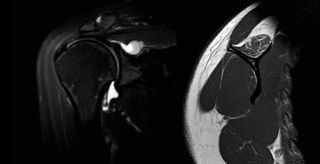

Left: MRA coronal view with T2 sequences revealing a large spinoglenoid cyst. Right: MRI sagittal view of the same patient with T1 sequences of a fatty infiltrated supraspinatus.